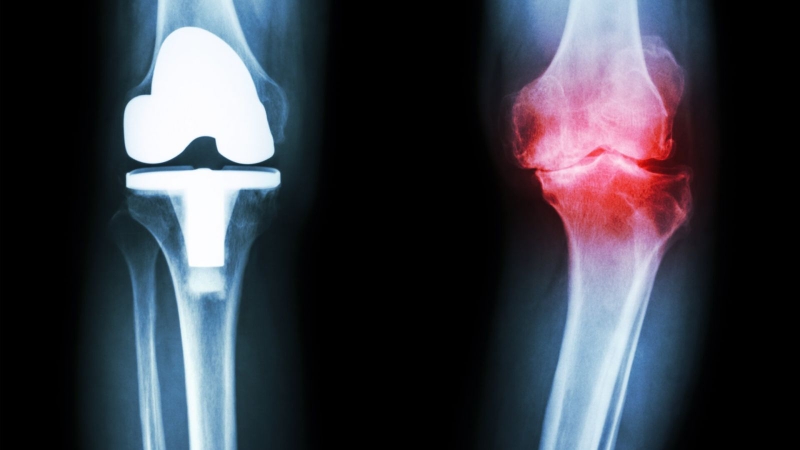

Chụp MRI não tốn hơn so với chụp đầu gối

Giá chụp MRI cũng có thể khác nhau tùy thuộc vào các bộ phận cơ thể. Ví dụ, chụp cắt lớp não có thể tốn nhiều chi phí hơn chụp đầu gối, vì nó đòi hỏi sự phân tích chi tiết hơn từ bác sĩ chuyên ngành.